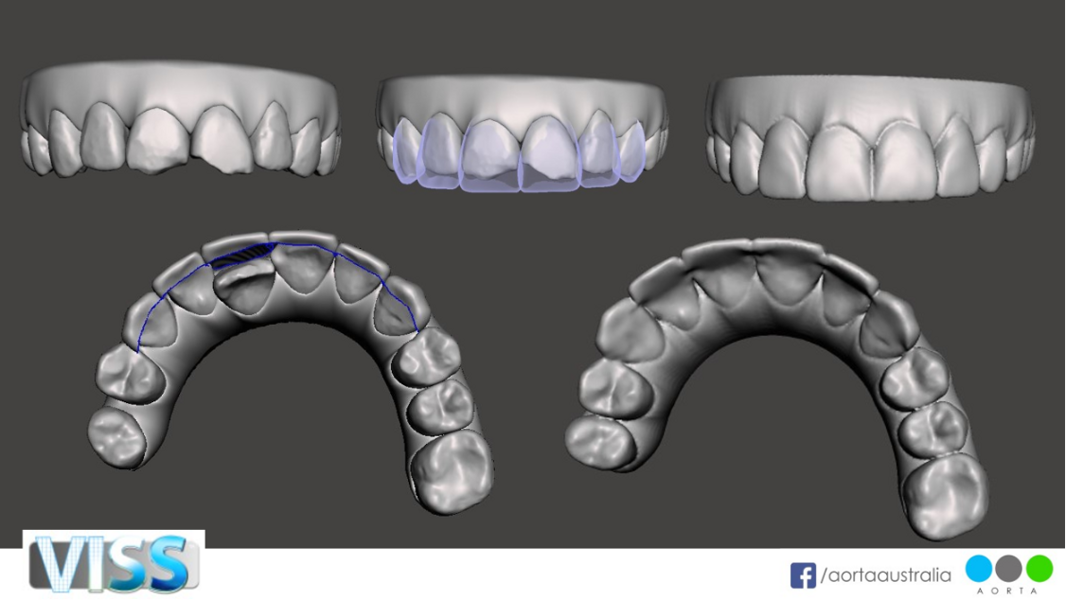

In this third section, we will explore how clear aligner simulations with Virtual Interdisciplinary Smile Simulation (VISS) can be digitally enhanced to demonstrate restorative augmentation after orthodontic treatment. This digital diagnostic and treatment planning service from AORTA digital laboratory has evolved since 2018 and is able to create a digital simulation of treatment with any aligner system, as well as of any direct or indirect restorative treatment or soft-tissue augmentation.

This concept of a virtual smile simulator evolved from the notion of seeking to create patients’ emotional connection to treatment through the clear aligner software. Its purpose is better smile creation by digitising the diagnosis, treatment planning and patient engagement process. This software enables the clinician to better diagnose and plan treatment using aesthetic orthodontic, prosthodontic and facial aesthetic principles from an extra-oral, perioral and dentition perspective.

When evaluating the STL files after clear aligner simulation of any aligner system, the clinician can assess whether there are hard- or soft-tissue augmentation options. From the soft-tissue perspective, if there is asymmetry of the zenith heights of the anterior gingival tissue or a need to lengthen tooth dimensions, this can be digitally simulated. The tooth perspective of the post treatment STL file can digitally simulate direct or indirect restorations to optimise the golden proportions regarding tooth length–width ratio. This can provide choices for both the clinician and the patient. This digital workflow can also provide superior informed choice pre- and post-treatment with clear aligners by simulating a restorative-only solution for comparison with the clear aligner simulation.

Figs. 34a–e: Simulated VISS images showing the situation pre-treatment (a & d), post-treatment (c & e) and after restorative treatment (purple).

Figs. 36a–e: Simulated VISS images showing the situation pre-treatment (a), post-treatment (b & e) and after restorative treatment (purple; c & d).